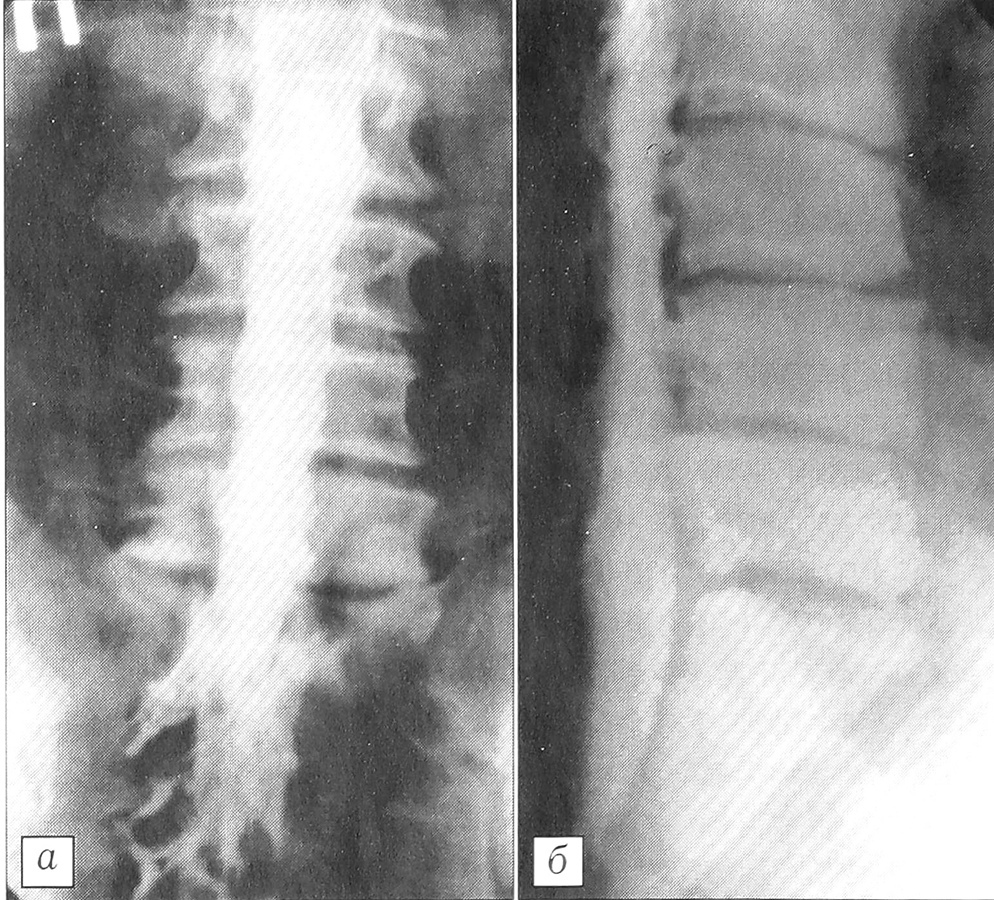

Рис. 5. Рентгенограммы (а — прямая, б — боковая) поясничного отдела позвоночника больного М. 16 лет. Остеохондропатия в сегментах L2-3, L3-4; уменьшение высоты L2~3, L3_4 межпозвонковых дисков, спондилоартроз.

Рис. 8. Рентгенограммы (а — прямая, б — боковая) поясничного отдела позвоночника больного О. 28 лет. Диффузная дегенерация поясничных дисков, спондилоартроз.